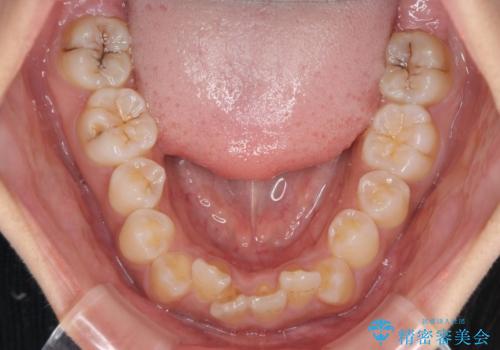

前歯のデコボコと隠れてしまう下顎前歯 インビザラインですっきりと改善

- 前歯のデコボコと、深い咬み合わせにより前歯が隠れていることを気にして来院された患者様です。

海外に長期滞在する予定があるとのことで、インビザラインにて矯正治療を行うこととしました。

インビザライン発注後に長期滞在先から2年間ほど帰国することができず、インビザラインの有効期限内に終了できるのか不安でしたが、矯正治療開始後は十分な装着時間を達成され、1年未満の期間で無事に終えることができました。